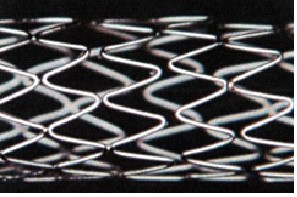

Стенты коронарные

В данную подсубпозицию включаются стенты коронарные, предназначенные для помещения внутрь пораженной части коронарного сосуда, где, расширяясь за счет эффекта «памяти» материала изготовления или с помощью баллона, выполняют функцию опорного каркаса для укрепления и поддержания стенок пораженного участка сосуда, обеспечивая нормальный кровоток по сосуду и нормальное кровоснабжение органа. Такие стенты могут быть изготовлены, например, в виде тонкой полой металлической или полимерной трубки

с ячейками либо из цельной круглой проволоки, которой сначала придается синусоидальная форма, а затем проводится спайка непрерывной синусоидальной конструкции. |

Примеры изображения стентов приведены ниже.